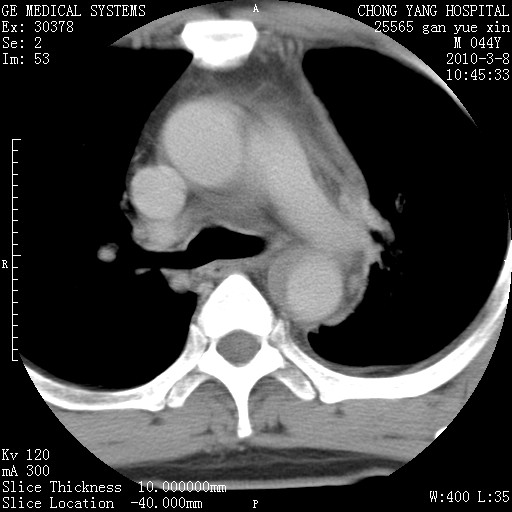

标题: CT24940:主动脉增强,典型病例。 [打印本页]

标题: CT24940:主动脉增强,典型病例。

夹层动脉瘤。

动脉夹层

夹层动脉瘤,典型

主动脉夹层。

动脉夹层的分型:

⒈debakey分型:根据主动脉夹层累及部位,分为三型:ⅰ型:原发破口位于升主动脉或主动脉弓部,夹层累及升主动脉、主动脉弓部、胸主动脉、腹主动脉大部或全部,少数可累及髂动脉。ⅱ型:原发破口位于升主动脉,夹层累及升主动脉,少数可累及部分主动脉弓。ⅲ型:原发破口位于左锁骨下动脉开口远端,根据夹层累及范围又分为ⅲa,ⅲb。ⅲa型:夹层累及胸主动脉。ⅲb型:夹层累及升主动脉、腹主动脉大部或全部。少数可累及髂动脉。

⒉stanford分型:a型:夹层累及升主动脉,无论远端范围如何。b型:夹层累及左锁骨下动脉开口以远的降主动脉。

夹层动脉瘤,少量胸水

夹层动脉瘤;左侧少量胸腔积液。

典型主动脉夹层。